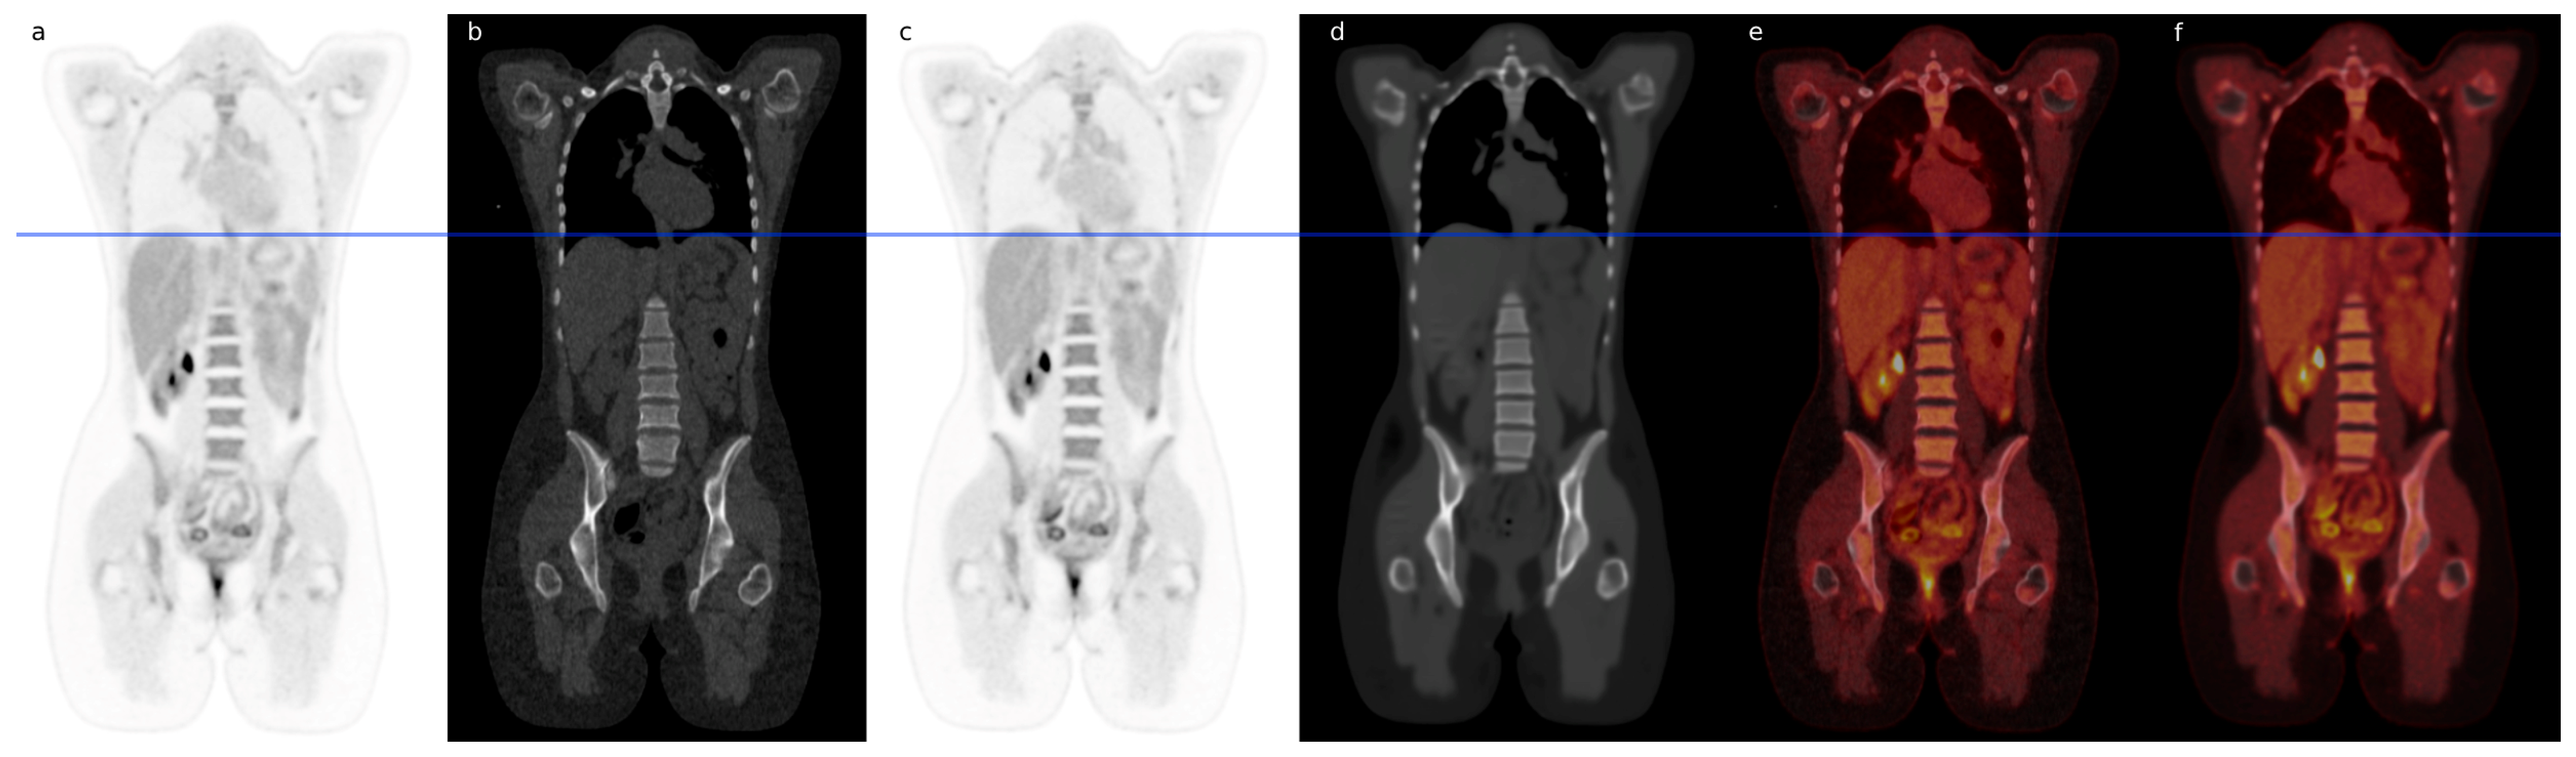

- Montgomery, M.E.; Andersen, F.L.; d’Este, S.H.; Overbeck, N.; Cramon, P.K.; Law, I.; Fischer, B.M.; Ladefoged, C.N. Attenuation Correction of Long Axial Field-of-View Positron Emission Tomography Using Synthetic Computed Tomography Derived from the Emission Data: Application to Low-Count Studies and Multiple Tracers. Diagnostics 2023, 13, 3661. [Google Scholar] [CrossRef]